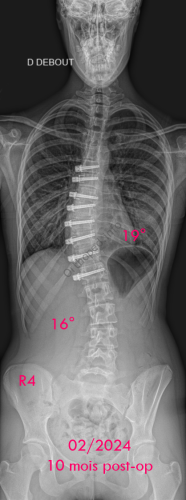

Images de scolioses opérées 16 janvier 202418 janvier 2023 par Damien Scoliose idiopathique - VBT -1 Chirurgie de modulation de croissance (VBT) Scoliose idiopathique - VBT -1 - pré-op Scoliose idiopathique - VBT -1 - pré-op en traction Cliché réalisé pour tester la réductibilité de la scoliose Scoliose idiopathique - VBT -1 - post-op immédiat Scoliose idiopathique - VBT -1 - 3 mois post-op Scoliose idiopathique - VBT -1 - 10 mois post-op